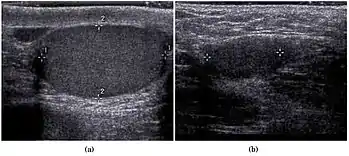

![]() Sonography of a normal testis. The normal testis presents as a structure having homogeneous, medium level, granular echotexture. The mediastinum testis appears as the

hyperechoic region located at the periphery of the testis as seen in this figure. | |

The normal adult testis is an ovoid structure measuring 3 cm in anterior-posterior dimension, 2–4 cm in width, and 3–5 cm in length. The weight of each testis normally ranges from 12.5 to 19 g. Both the sizes and weights of the testes normally decrease with age. At ultrasound, the normal testis has a homogeneous, medium-level, granular echotexture. The testicle is surrounded by a dense white fibrous capsule, the tunica albuginea, which is often not visualized in the absence of intrascrotal fluid. However, the tunica is often seen as an echogenic structure where it invaginates into the testis to form the mediastinum testis. In the testis, the seminiferous tubules converge to form the rete testes, which is located in the mediastinum testis. The rete testis connects to the epididymal head via the efferent ductules. The epididymis is located posterolateral to the testis and measures 6–7 cm in length. At sonography, the epididymis is normally iso- or slightly hyperechoic to the normal testis and its echo texture may be coarser. The head is the largest and most easily identified portion of the epididymis. It is located superolateral to the upper pole of the testicle and is often seen on paramedian views of the testis. The normal epididymal body and tail are smaller and more variable in position.